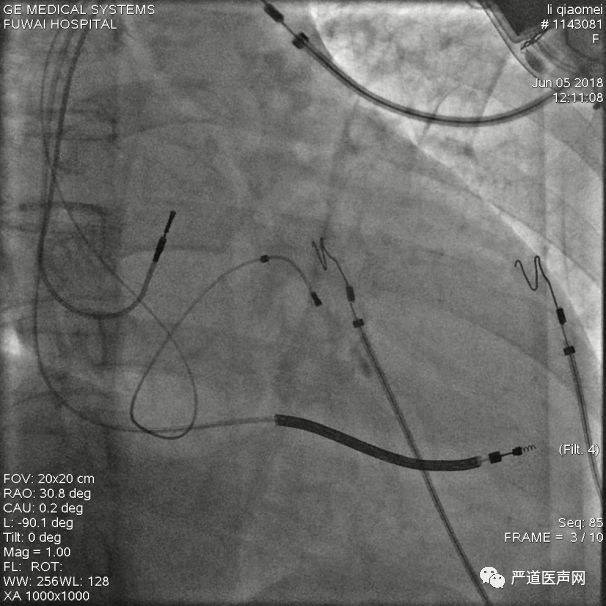

鞘管位置较低且向远端推送有阻力,考虑可能超选进入后静脉,需造影确定鞘管位置

经长鞘直接造影确定鞘管位置

造影示鞘管已经超选进入后静脉,不在冠状窦主干内,同时侧静脉及冠状静脉主干显影。可见冠状静脉主干向上,走形角度较大